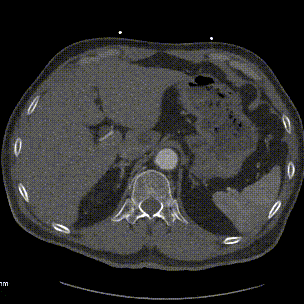

案例三(梯形瘤颈):3年前肾结石,在治疗复查过程中发现腹主动脉瘤。

案例四(梯形瘤颈):因下肢髋部疼痛行腰椎检查时发现腹主动脉瘤,进一步CTA认证确诊为腹主动脉瘤。

案例五:查体发现腹主动脉,行CTA确认腹主动脉瘤伴血栓形成。